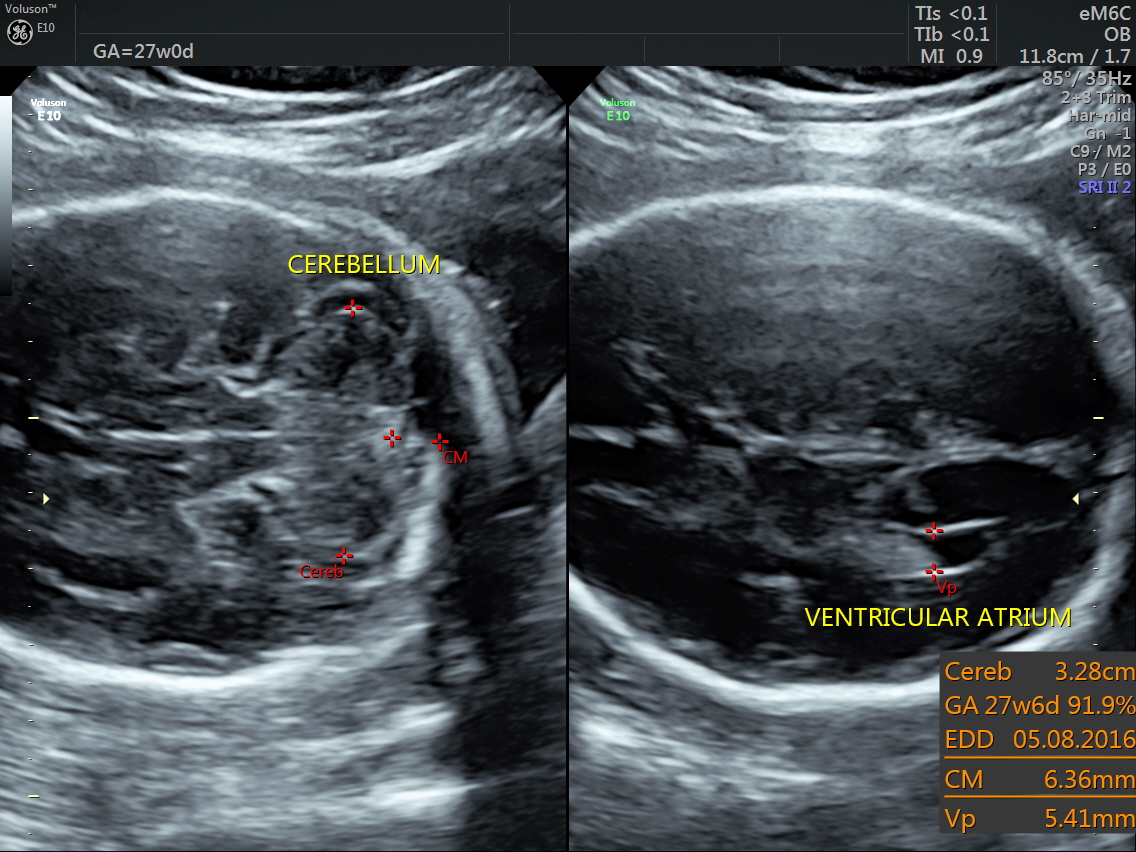

RT AORTIC ARCH_5 Published June 17, 2016 at 1136 × 852 in Rt aortic arch and aberrant left subclavian artery ← Previous Next →